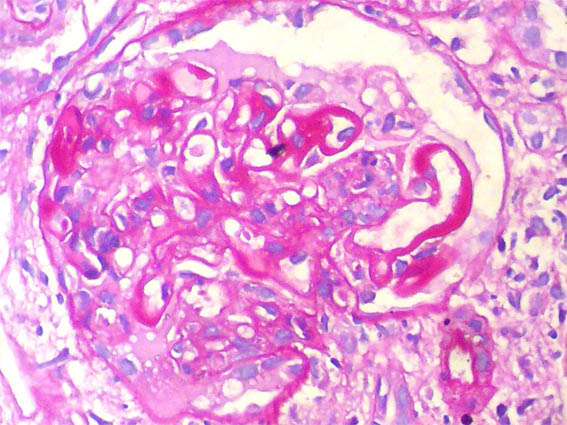

A renal biopsy was done, see the images.

Figure 4. H&E, X400.